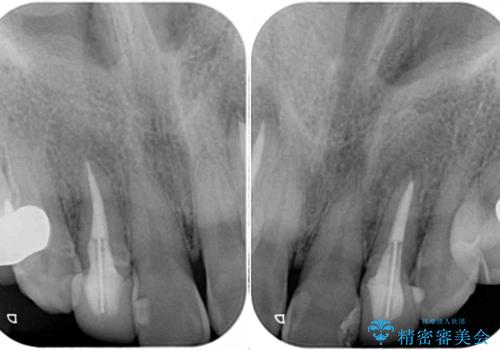

- クラウンから金属の土台が見えてきてしまったとのことで、作り替えを希望して来院された患者様です。

前歯や金属が露出している歯、痛みを感じる歯を中心に、オールセラミッククラウンにて補綴治療することとしました。

以前はセラミッククラウンのフレームとして金属が使用されており、歯肉の経年変化やセラミックのすり減りなどにより、金属が見えるようになってくることがあります。